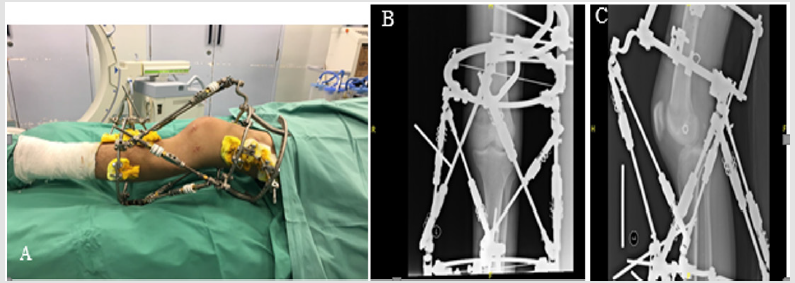

Both patients were satisfied with their outcome. Good reductions of their knee joints were obtained as per radiographic evidence. Resulting knee functions were graded “fair” for the first patient and “good” for the second patient based on Lysholm Knee Scoring Scale. Apart from mild pin tract infections no other complications occurred during their course of treatment (Figures 1 & 2, Table 1).

Figure 1: Postoperative knee photograph and plain radiographs of one of the patients. A. Ortho-SUV frame applied in-situ across the dislocated knee. B. AP view and C. lateral view plain radiographs demonstrating the posterior knee dislocation.